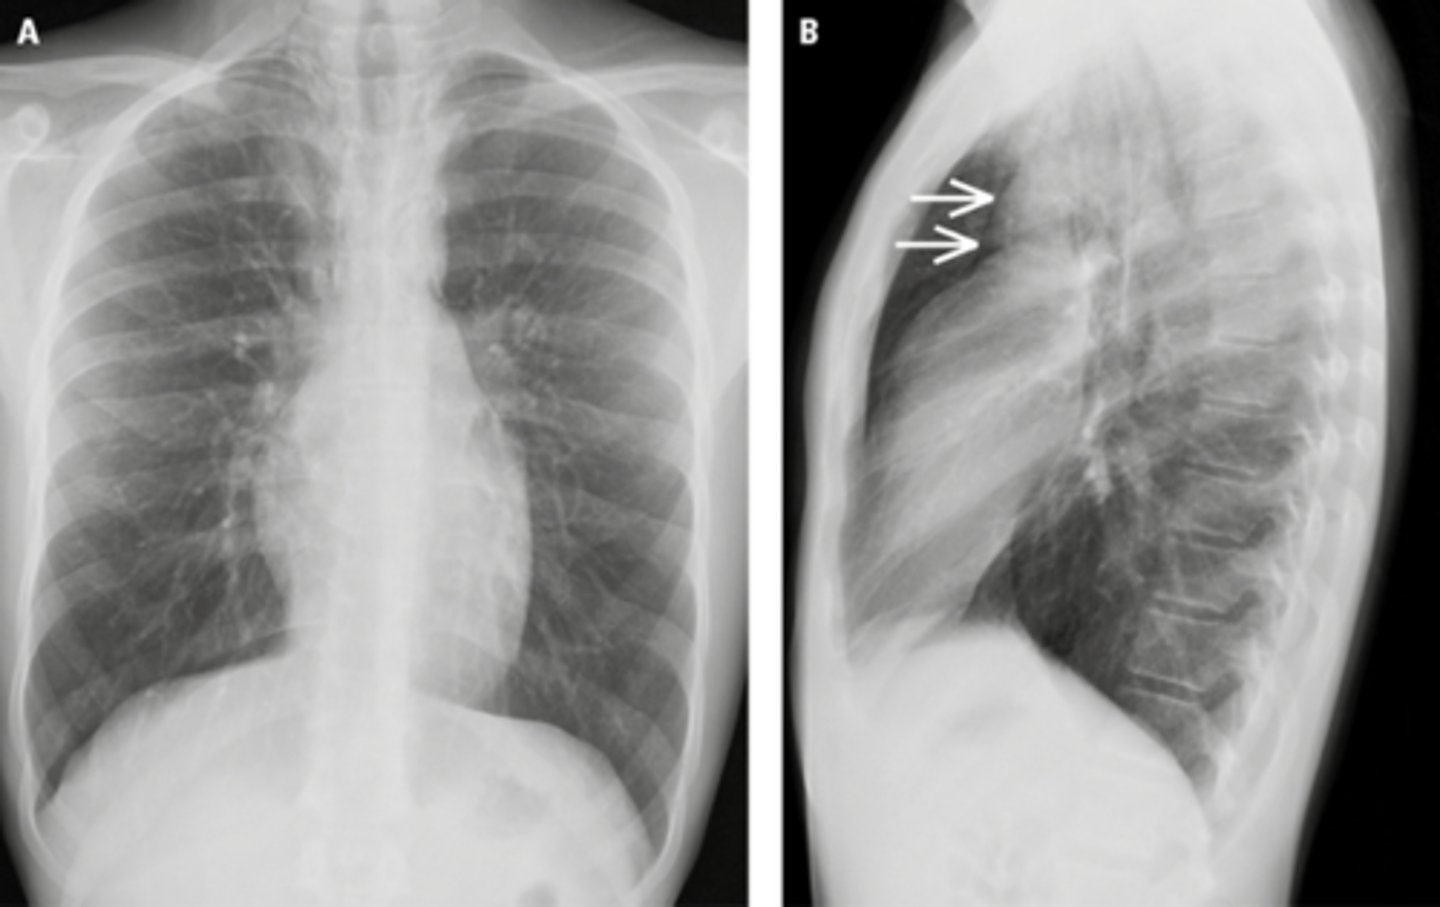

Bronchiectasis

knowt flashcard image

Tram track lines